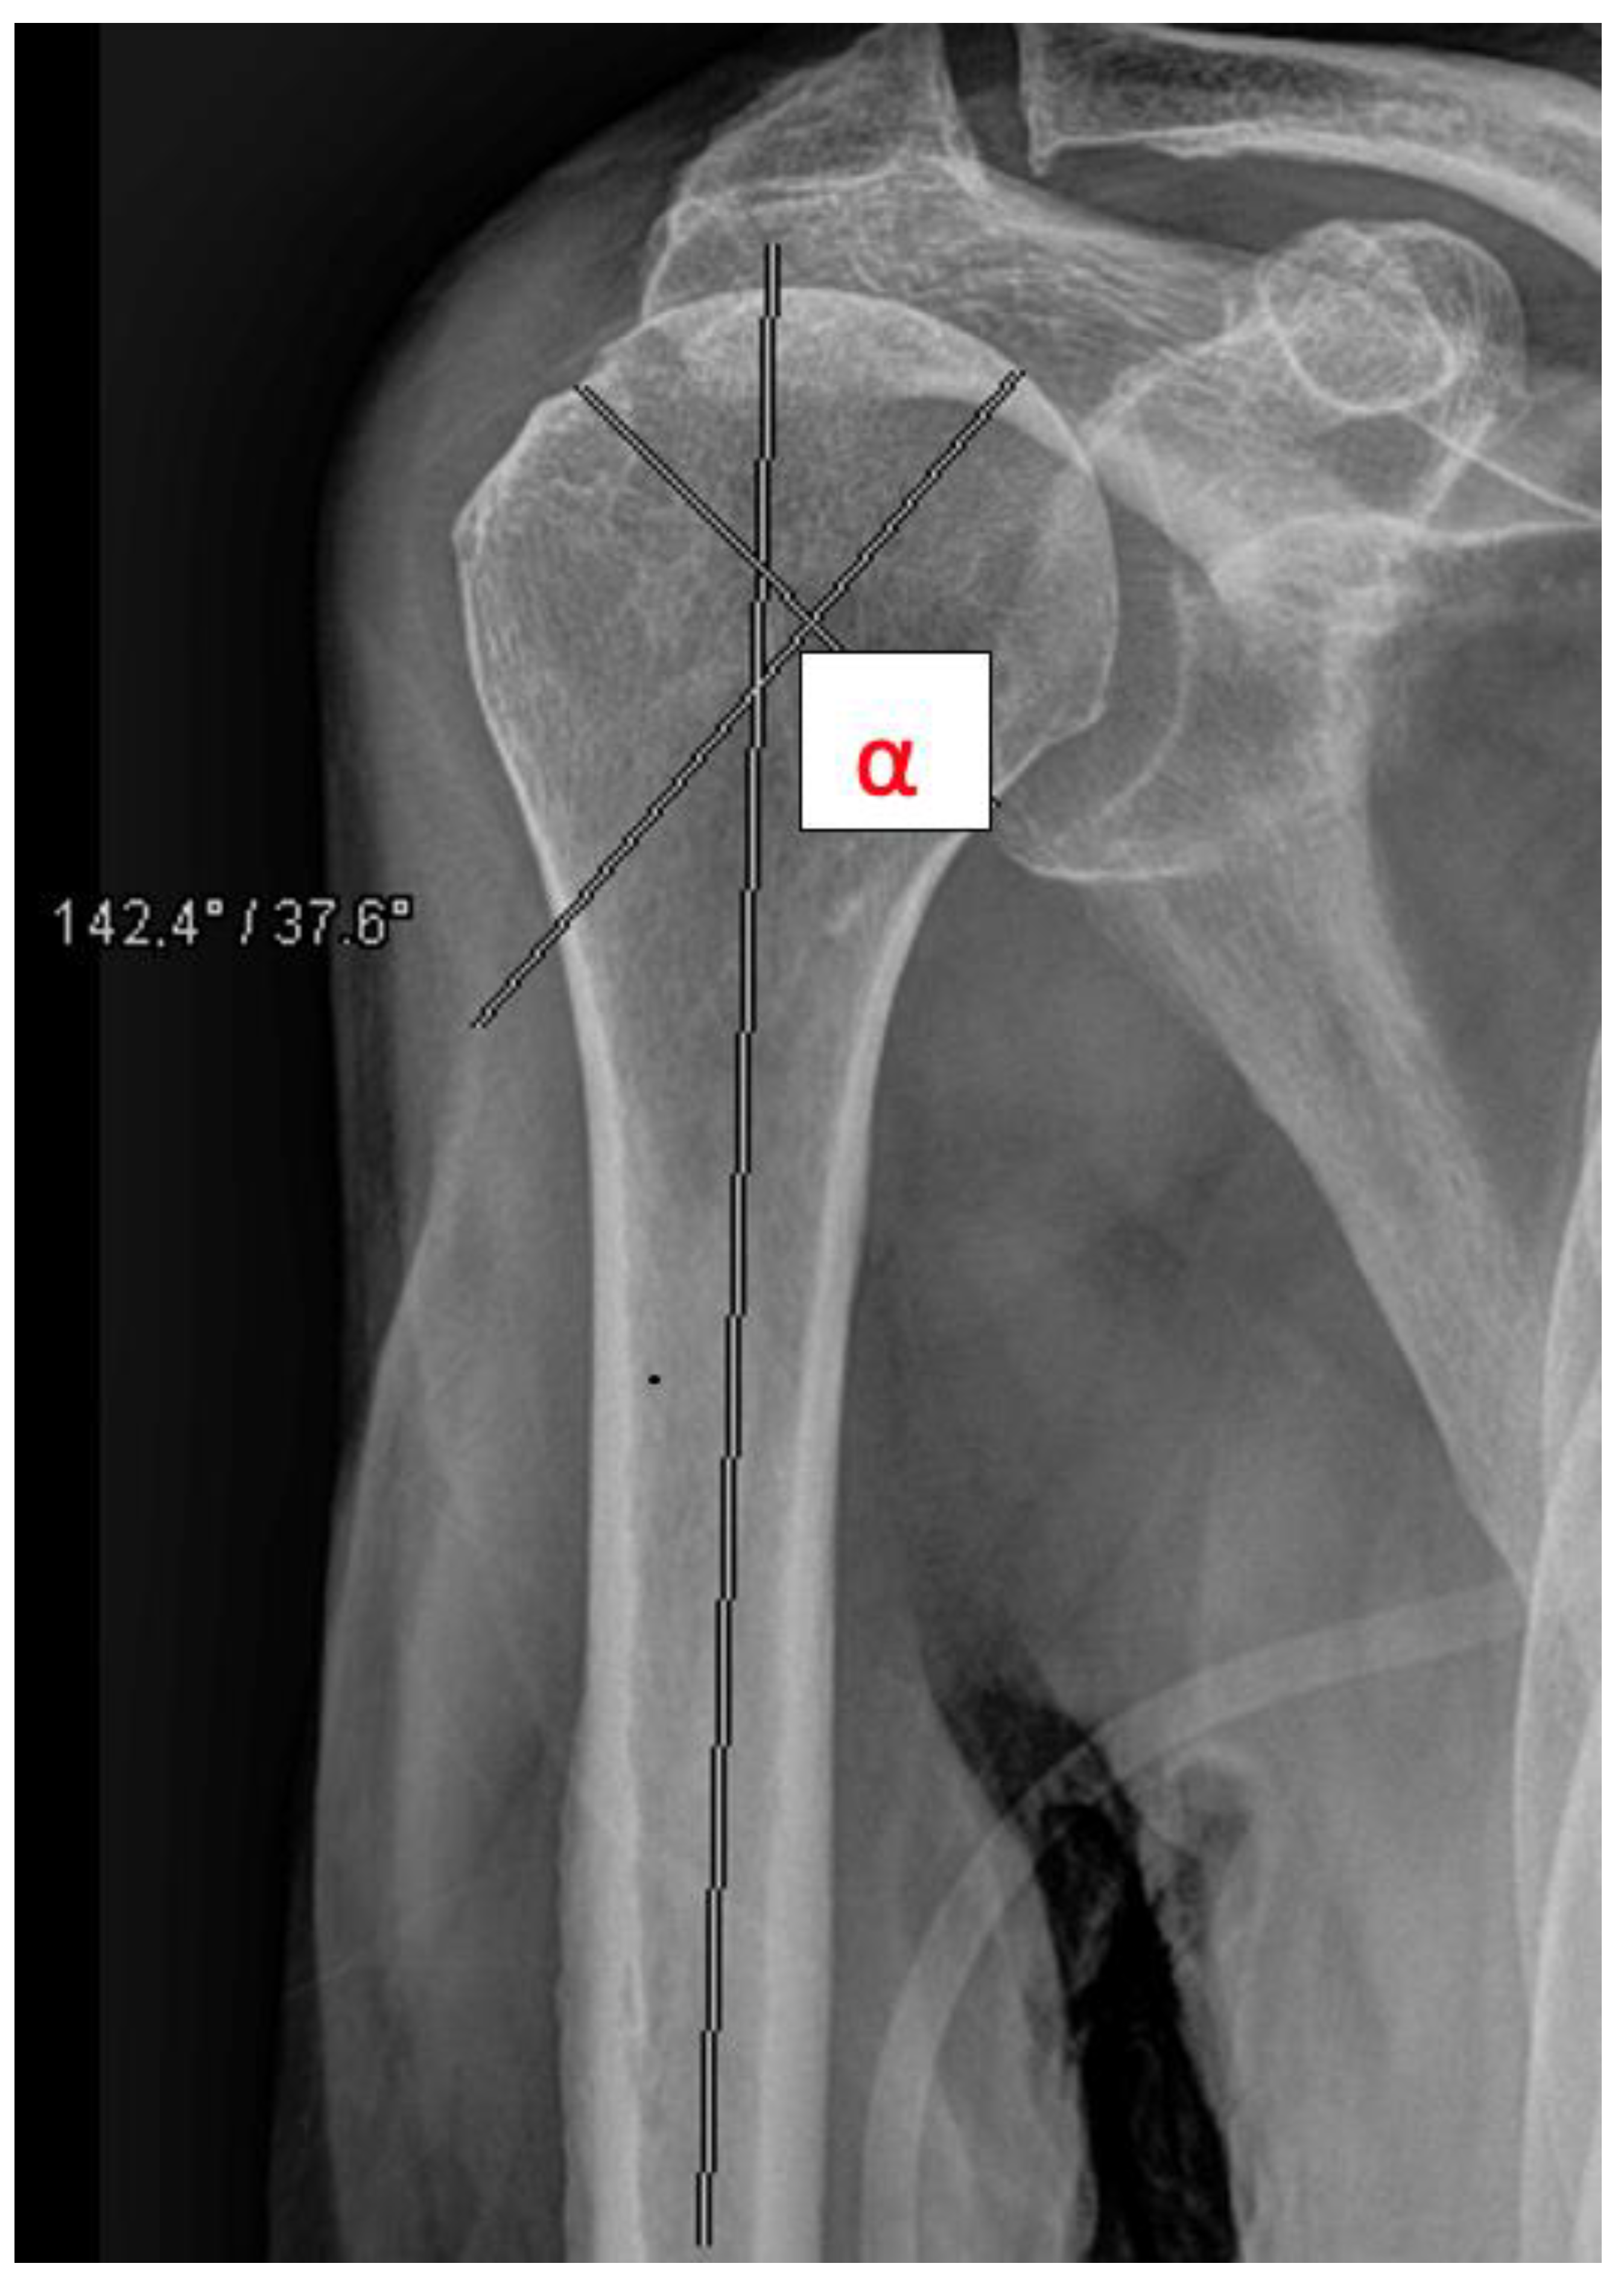

The head-shaft angle (HSA) was measured by a resident and a consultant radiologically preoperatively, postoperatively, and after 6 weeks in all fractures except A1 fractures (Figure 4). Primary outcome measures included secondary dislocation and surgical complications. Secondary outcome measures included function after 3 months, mortality, and discharge disposition. A one-year follow up to obtain information about the mortality and complications was performed by analyzing the electronic record of the patient. In the geriatric and partly immobilized collective, many patients were not seen as outpatients. In these cases, follow up was performed by phoning the patients.

Figure 4. Measurement of the head shaft angle (HAS, e.g., 14.2°).